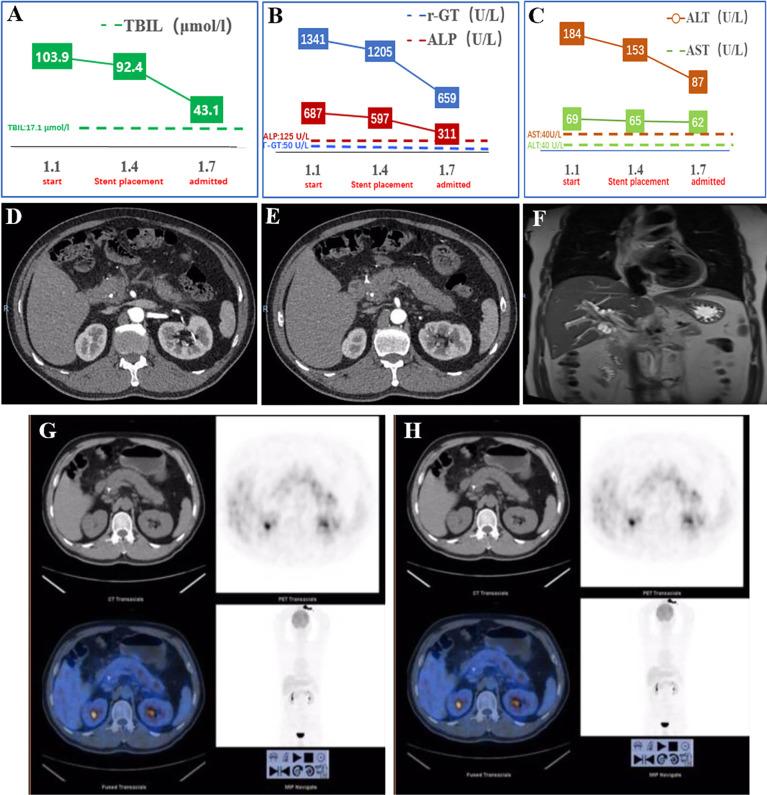

A 57-year-old male patient was transferred to our hospital after endoscopic retrograde cholangiopancreatography (ERCP) with stent placement in the common bile duct due to obstructive jaundice at a local hospital. Groove pancreatitis was considered based on the clinical manifestations and multiple examinations [including computed tomography (CT), magnetic resonance cholangiopancreatography (MRCP), and endoscopic ultrasonography (EUS)]. The patient's symptoms and laboratory results almost returned to normal after conservative treatments. Interestingly, his symptoms and laboratory results worsened after the stent was removed. We performed a second EUS process and found a lesion in the lower common bile duct. Finally, the patient underwent pancreatoduodenectomy, and the diagnosis was confirmed as moderately differentiated adenocarcinoma of the common bile duct.